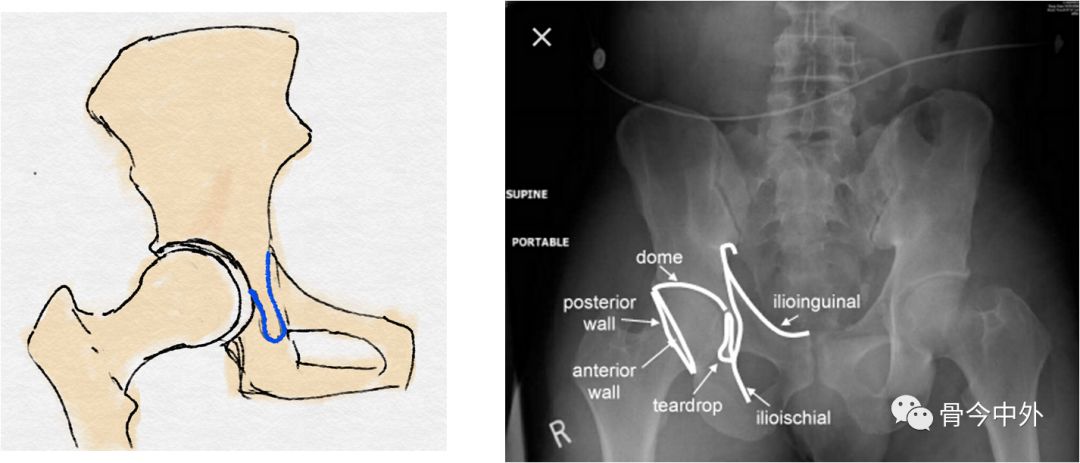

泪滴:

U型的弧线

代表了髋臼的内缘

前唇线:

髋臼前缘所连成的弧线(左图中蓝线)

反映髋臼前壁的完整性

后唇线:

髋臼后缘所连成的弧线(左图中红线)

反映髋臼后壁的完整性

8字征:

髋臼前缘与后缘交叉

提示髋臼撞击综合征